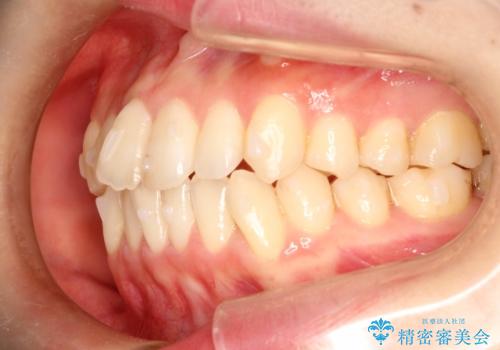

前歯のガタガタをインビザラインで目立たず矯正

- 目立たずに前歯を矯正したいとのことで来院されました。

歯と歯の間にわずかに隙間を作りスペースを確保し、インビザラインにて矯正を行うこととなりました。

前歯の微調整に少し時間がかかりましたが、整った歯並びにすることができました。